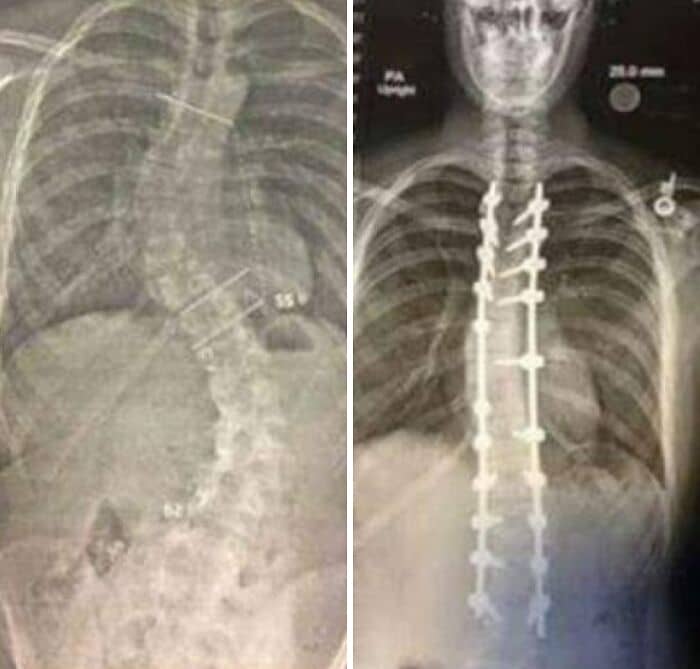

#10 These Are X-Rays Taken Before And After The Surgery

It has been 4 years to the day since I had my scoliosis surgery. The surgery itself took 14 hours. Surgeons drilled metal straightening bars into my spine.

#46 Before And After Hip Replacement Surgery